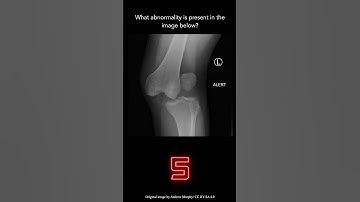

M Question Musculoskeletal Documentation Part 2